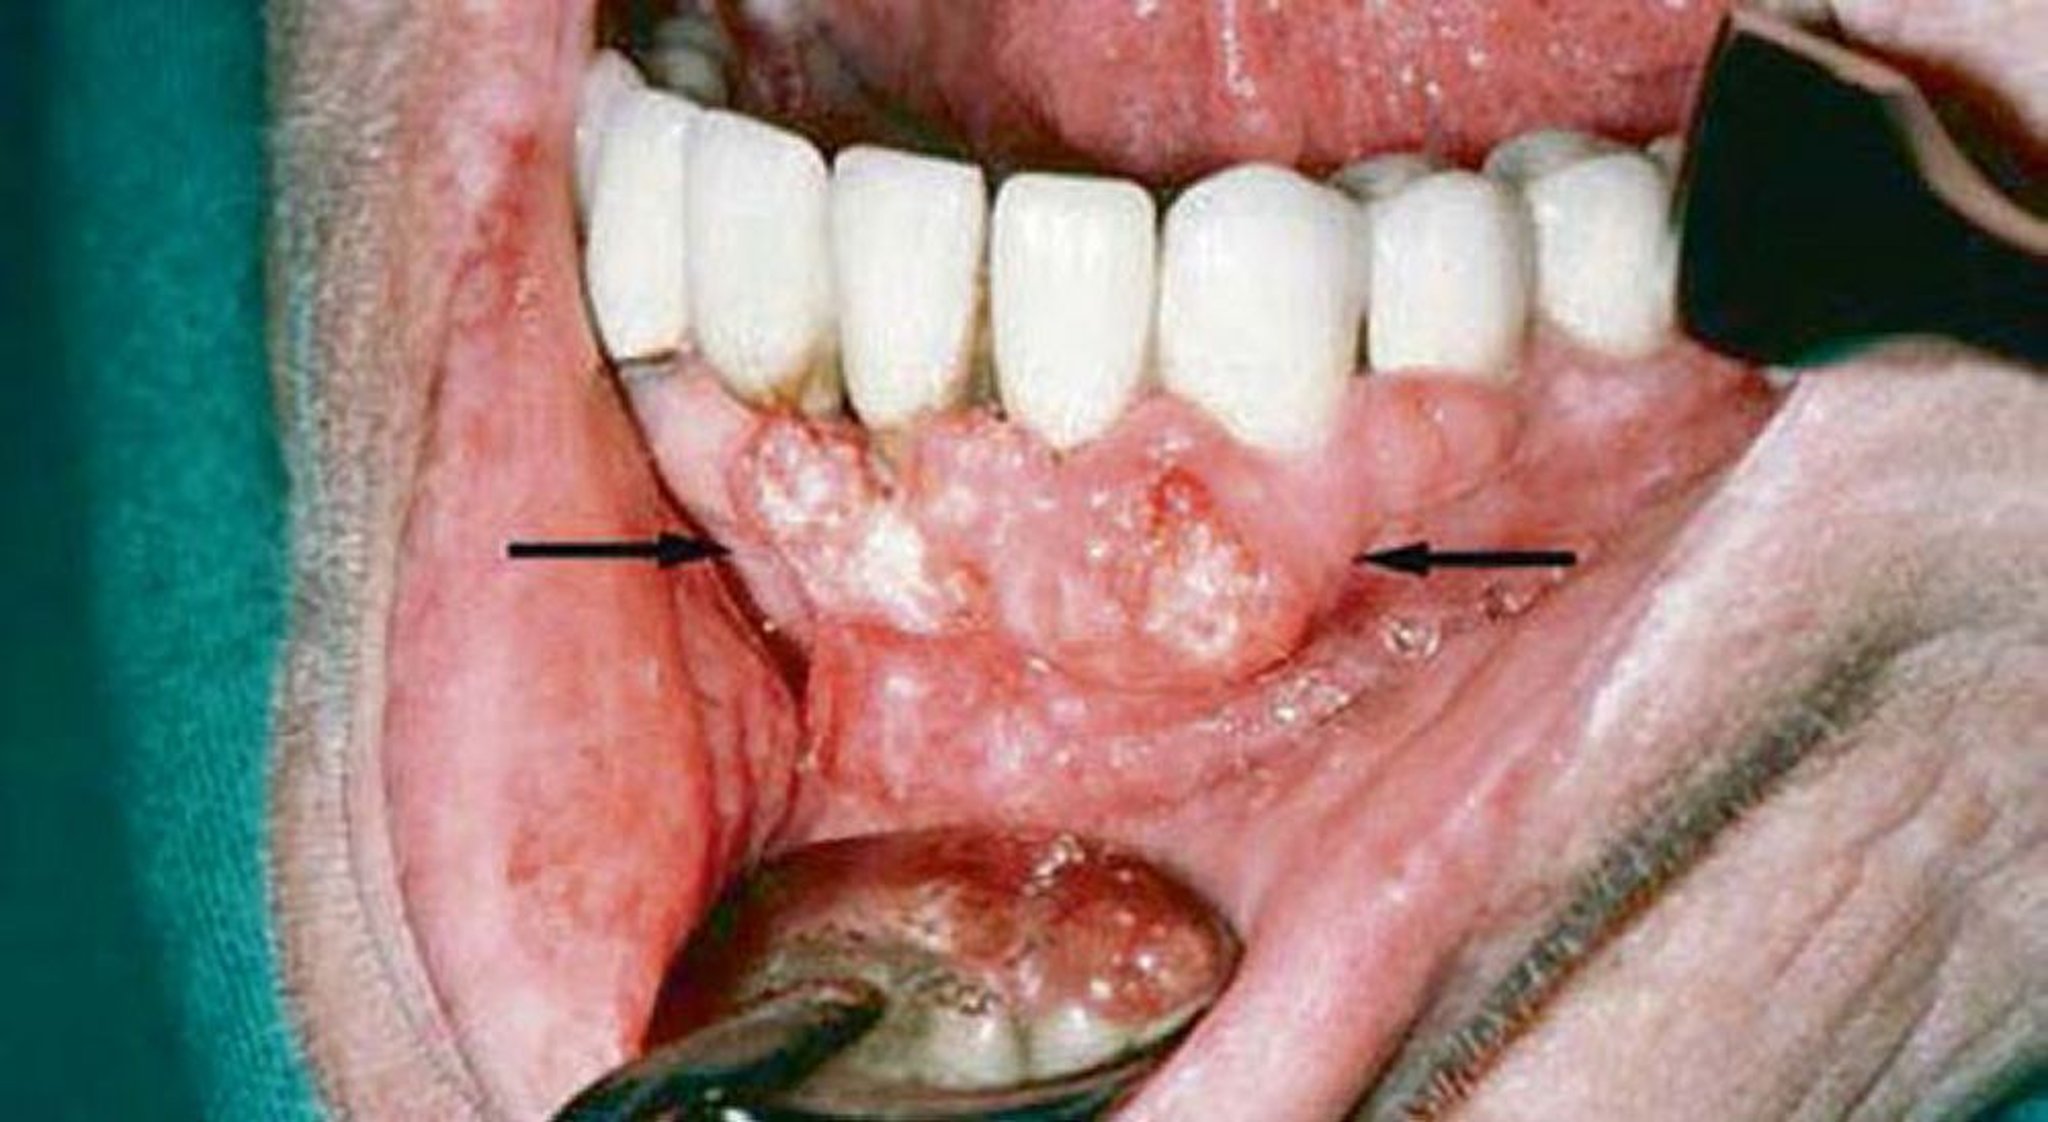

Plattenepithelkarzinom (Gingivaläsionen)

Die gingivale Untersuchung dieses Patienten zeigte Hinweise auf ein Plattenepithelkarzinom. Bildgebende Untersuchungen zeigten eine Invasion in den Unterkiefer.